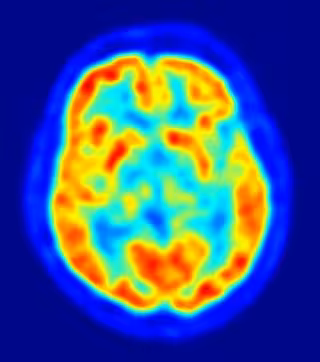

Una de las características de la enfermedad de Alzheimer es la acumulación en el cerebro de la proteína betaamiloide. De hecho, con el tiempo estas proteínas se acumulan con tal densidad que se pueden observar en forma de placas en las exploraciones del cerebro. Comprender el papel que juega el sistema glymphatic en la incapacidad del cerebro para descomponer y eliminar la betaamiloide podría señalar el camino a nuevos tratamientos. En concreto, unos "actores" clave en el sistema glymphatic, como los astrocitos, se pueden manipular hasta la eliminación de los residuos.